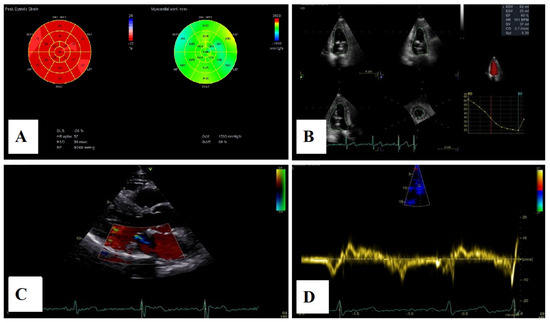

Echocardiographic assessment demonstrated a reduction in left atrial and ventricular volumes, as measured by three-dimensional volumetry, with improvement in left atrial contractile function. Mitral regurgitation remained mild, and no recurrence of mitral annular disjunction was noted (Figure 11). Tricuspid regurgitation remained mild throughout the follow-up period, with a slight reduction in right atrial and ventricular dimensions and preserved right ventricular function.

Figure 11.

(A)—2D speckle-tracking echocardiography, displaying normal global longitudinal strain (−20%) and myocardial work bull’s-eye plot, displaying normal range of GWI (global work index—1533 mmHg%). (B)—Left ventricular volumetry and systolic function assessed by 3D echocardiography, showing normal volumes and ejection fraction—EF–60%. (C)—The parasternal long-axis view displays trivial mitral regurgitation without mitral annular disjunction. (D)—Tissue Doppler imaging on the lateral mitral annulus, without Pickelhaube sign.